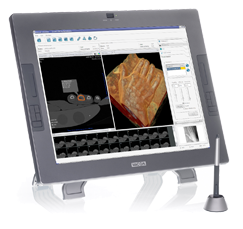

Interested in purchasing VivoLab? We're pleased to hear it. Find out how to purchase VivoLab by contacting our sales department at sales@digitalmedics.de and a sales representative will contact you as soon as possible.